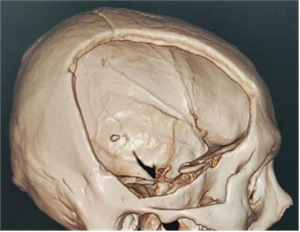

病例 2:42 岁男性因车祸伤进行开颅术后,遗留颅骨缺损,同样接受了自体颅骨修补术。

术前:

术中: